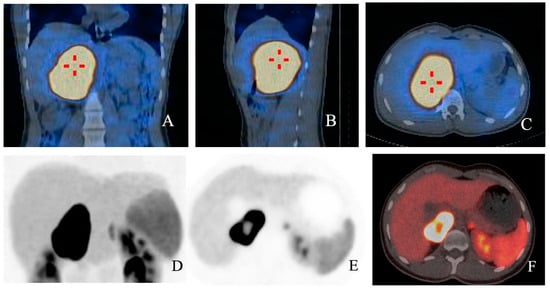

- Galatola, R.; Attanasio, L.; Romeo, V.; Mainolfi, C.; Klain, M.; Simeoli, C.; Modica, R.; Guadagno, E.; Aprea, G.; Basso, L.; et al. Characterization of Atypical Pheochromocytomas with Correlative MRI and Planar/Hybrid Radionuclide Imaging: A Preliminary Study. Appl. Sci. 2021, 11, 9666. [Google Scholar] [CrossRef]

- Galatola, R.; Romeo, V.; Simeoli, C.; Guadagno, E.; De Rosa, I.; Basso, L.; Mainolfi, C.; Klain, M.; Nicolai, E.; Colao, A.; et al. Characterization with hybrid imaging of cystic pheochromocytomas: Correlation with pathology. Quant. Imaging Med. Surg. 2021, 11, 862–869. [Google Scholar] [CrossRef] [PubMed]